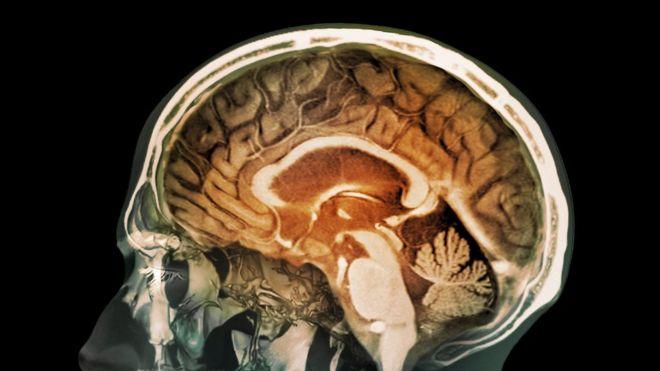

Los desechos tóxicos de la contaminación del tráfico pueden, literalmente, llegar a tu cerebro.

Al menos eso se desprende de la evidencia presentada en un estudio realizado en muestras de tejido cerebral.

Investigadores de la Universidad de Lancaster, Inglaterra, descubrieron que pequeñas partículas de metal que se desprenden de los gases de escape de la combustión pueden introducirse por la nariz y viajar hasta el cerebro humano.

Una vez allí, sugieren los científicos, pueden causar daños en el cerebro y contribuir, por ejemplo, a la enfermedad de Alzheimer.

Pero se piensa que las nanopartículas de la magnetita son tan diminutas que pueden pasar desde la nariz y el bulbo olfatorio hacia el sistema nervioso y hasta la corteza frontal del cerebro.